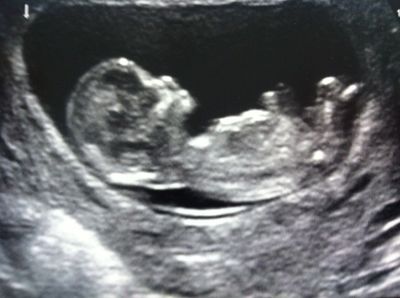

Los defectos del tubo neural:

Image:

e81b1366-1e4c-4eb0-b6a5-e134f621b614 (image/jpg)

Answer

A- La espina bífida oculta suele ser asintomática-

B- Son las malformaciones congénitas del SNC más frecuentes-

C- Se definen como defectos de la médula espinal-

D- Se suelen asociar a una reducción de la alfafetoproteína sérica materna durante la gestación-

E- La espina bífida quística produce mielomeningocele o meningocele-